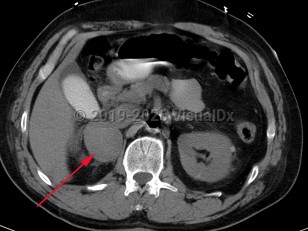

PheochromocytomaPheochromocytoma